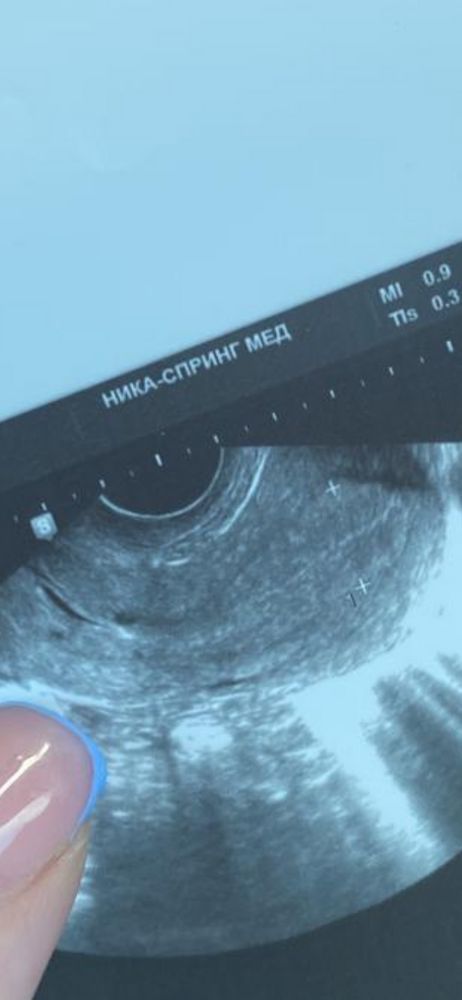

Здравствуйте, сегодня на узи доминантный фолликул-20.4мм, а эндометрий 16.6мм, это слишком ли большой эндометрий?

Вот так выглядит на фото , может ли прикрепится к такому ?

Оптимальная толщина эндометрия для имплантации составляет 11 - 14 мм. Недостаточная толщина помешает проникновению и фиксированию яйцеклетки к маточной стенке. Избыточная толщина повышает риск отторжения плодного яйца.В норме толщина постепенно увеличивается с 3 мм в первой фазе до 15 мм во второй, а при гиперплазии этот показатель составляет более 15,5 мм При эко мне врач говорила,что эндик должен быть от 8 до 12 мм, больше или меньше-перенос эмбриона под вопросом,т.к.это может помешать имплантации